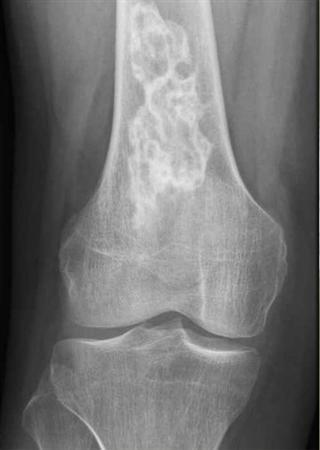

Diagnosis?

Bone Infarct